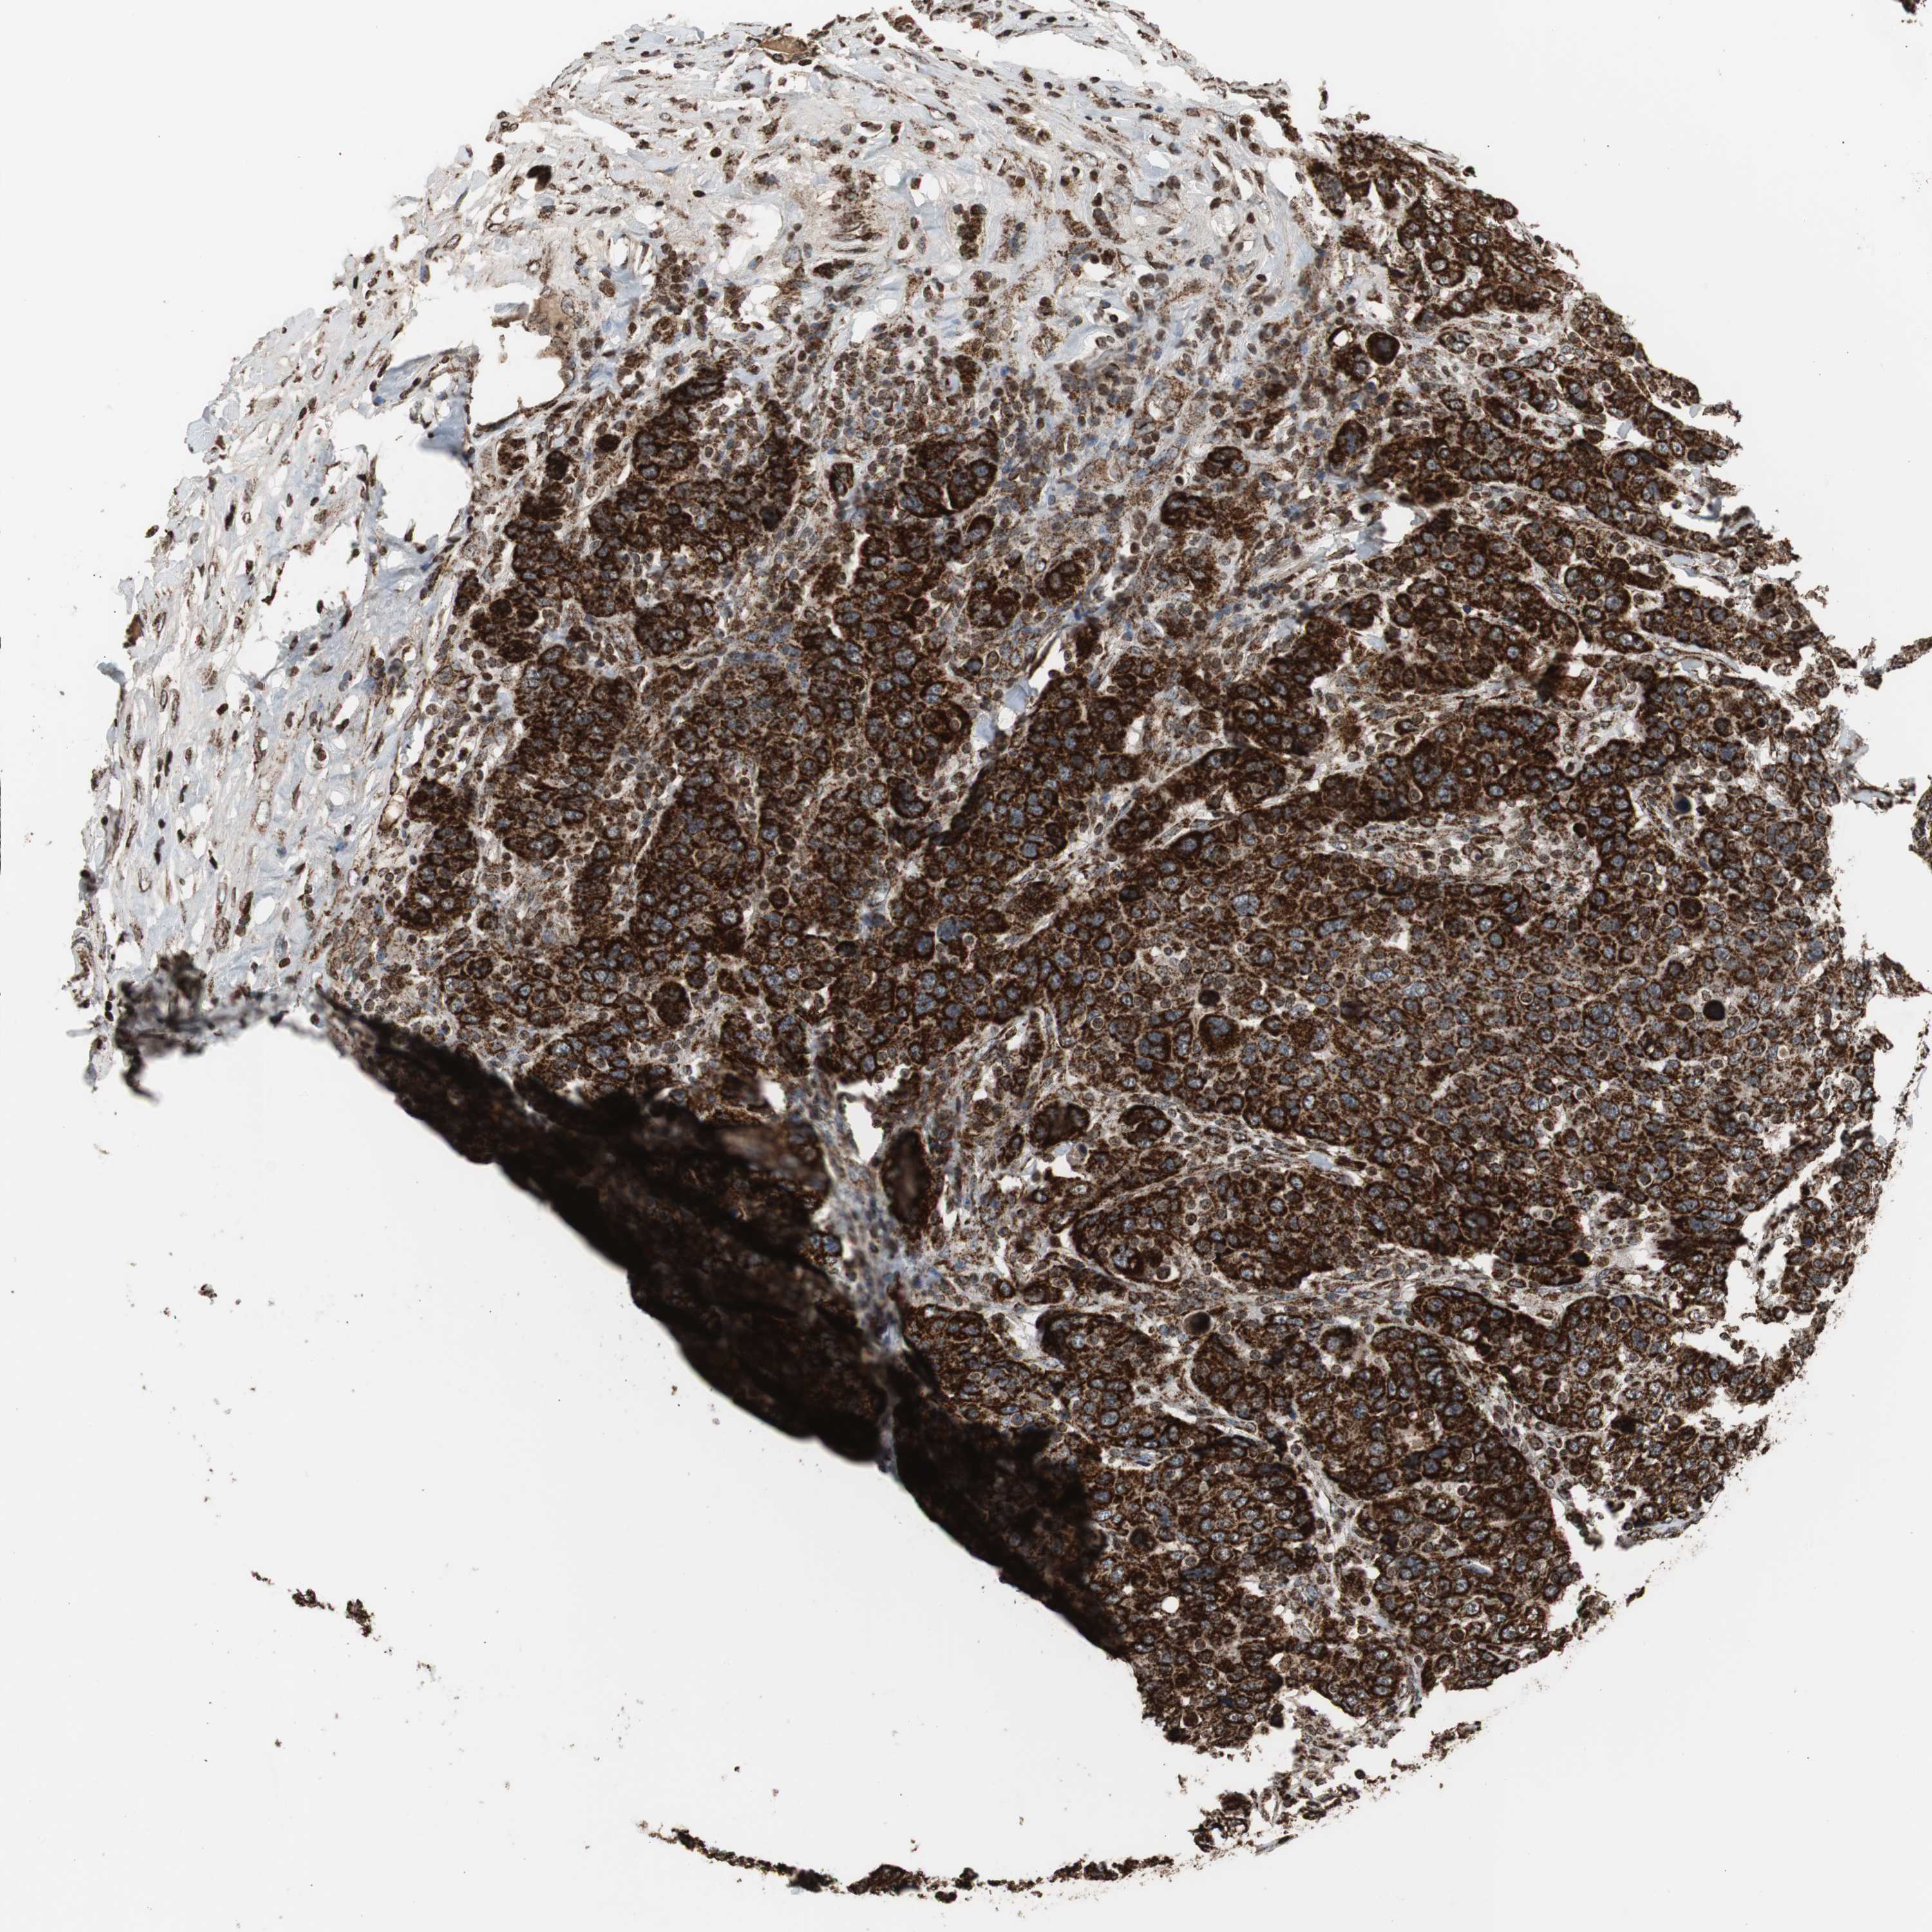

CANCER BREAST CANCER Show tissue menu

BRCA TCGA BRCA VALIDATION PROTEIN EXPRESSION